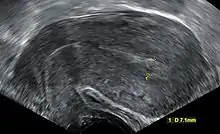

| An ultrasound showing a gestational sac containing a yolk sac but no embryo. | |